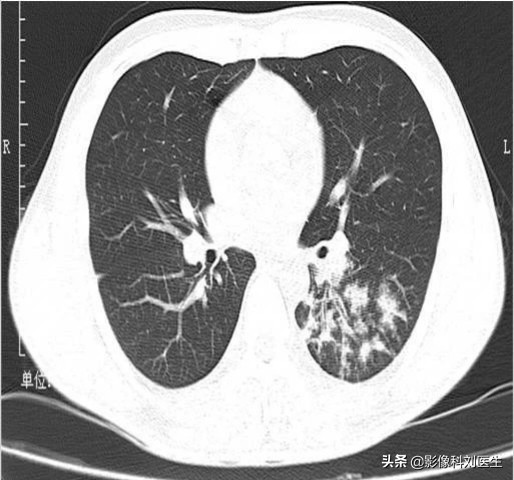

支气管肺炎累及多肺叶、多肺段,沿支气管血管束分布,下叶多见,常表现为多发、边界不清的结节样阴影,为腺泡结节,多位于小叶中央;部分呈磨玻璃密度影,部分病灶可融合;由于炎症导致终末细支气管阻塞,可引起局限性肺气肿,当化脓感染时,可出现大小不等的空洞。

CT 表现:表现为两肺中下野内中带云絮状、斑片状、结节状高密度影,沿支气管走行分布,边缘模糊,散在的小片状影,可以融合成大片状,可并发小叶性肺气肿及肺不张。